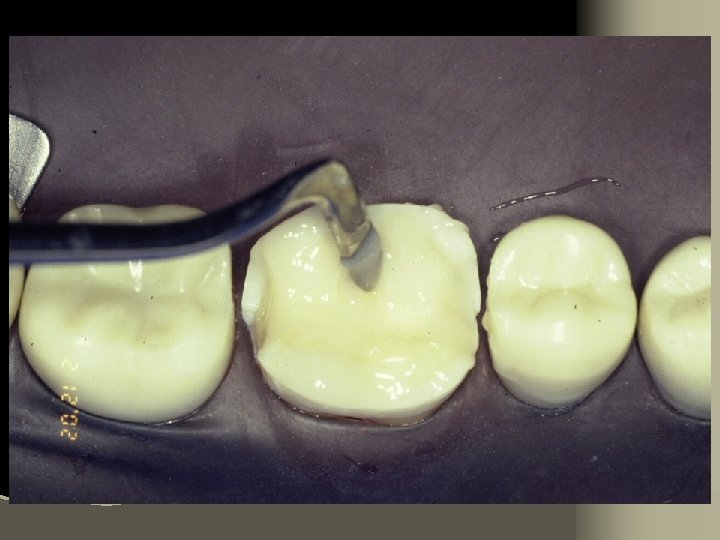

Mix 10 -20 seconds

Remove excess cement

Light cure all surfaces 60 seconds each

Conventional composite finishing techniques